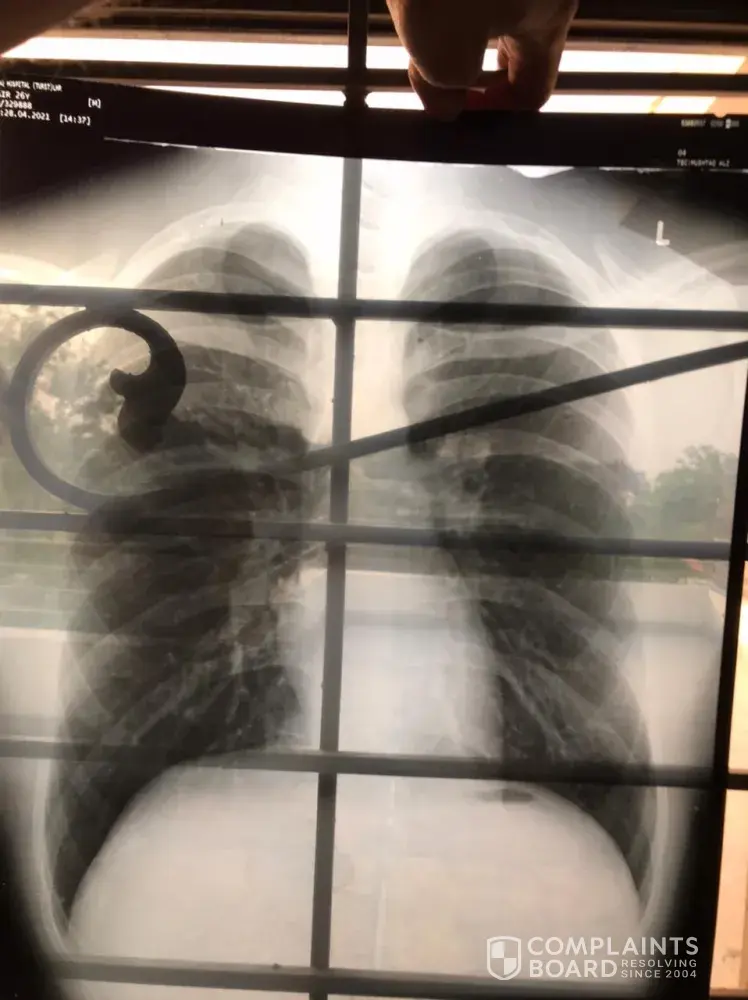

I had Appointment on 16th April 2021 which is Already done. On (04/28/2021) i received call from QVC Islamabad to retake the Chest X-ray on (05/27/2021) because of some problem came up and upon asking them they don't have any solid reason to give. It can be a medical problem in chest or it can be technical issue. just because of that i went to hospital to check if there is any medical issue in Chest but reports were clear. i have to spend all the way to go to different city for this X-ray which they haven't done in professional way and with Faulty Reports. i would like to show my X-ray which is done on the same day of receiving the call From Qvc Islamabad (04/28/2021) And X-ray is Clear.

Kindly Take Action on this Unprofessionalism of Doctors sitting in QVC Islamabad And Replace them with Good and Professional Doctors, Our whole Medical Relies on them which they send to MOH (Ministry Of Health Qatar)

Desired outcome: Replace The Doctors.